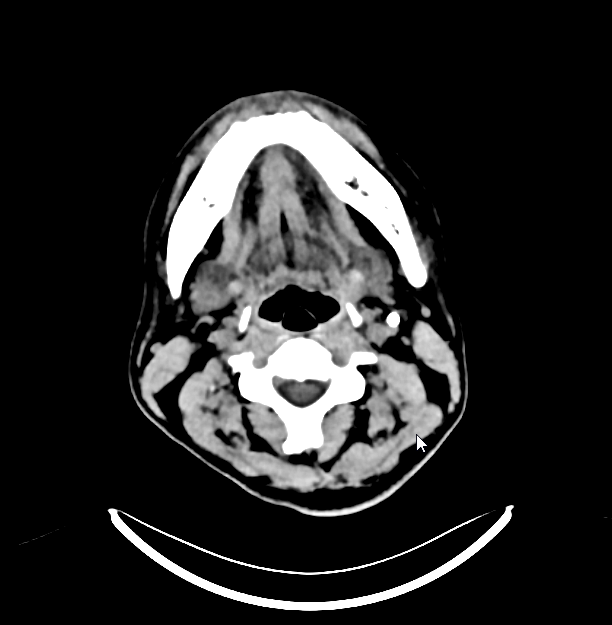

术后停用口服抗凝药,经两根溶栓微导管分别给予50万单位尿激酶持续泵入,经导引导管给予5000U肝素持续泵入,持续6天。 患者术后第2天意识恢复正常,并诉头痛减轻,复查头颅CT未见出血。

术后第6天复查动脉造影,计划必要时调整溶栓导管位置,显示静脉窦内血栓完全消失,遂拔出导管和鞘管。